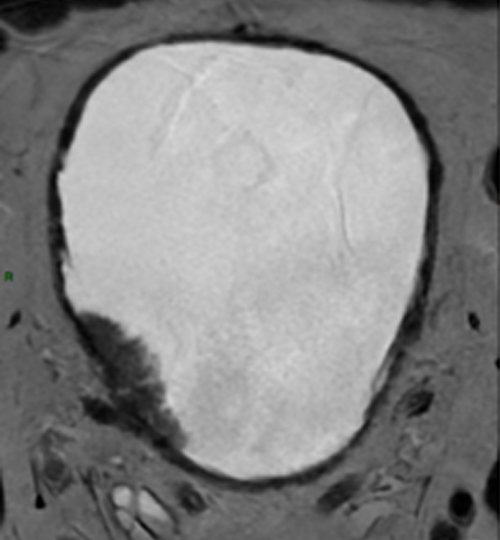

Le terme « polype de vessie » est une expression impropre utilisée pour décrire les tumeurs n’infiltrant pas le muscle. Il cache en réalité une maladie toujours cancéreuse et parfois grave. Le Dr Masson-Lecomte (hôpital Saint-Louis, Paris) fait le point sur les signes cliniques évocateurs, le bilan initial, la prise en charge actuelle et les modalités de surveillance.